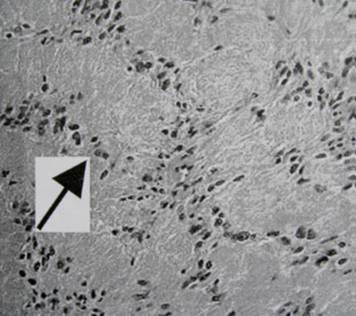

33.Seorang laki-laki gemuk usia 28 tahun dibawa dengan riwayat sakit kepala dan diplopia selama dua bulan terakhir. Ternyata pasien mengalami lesi sebagaimana yang ditunjukkan pada fotomikrograf di bawah in. Apakah yang dijelaskan oleh tanda panah pada fotomikrograf tersebut?

A. Telangiestasia kapilaris

B. Gemitosit

C. Serat Rosenthal

D. Pembuluh darah normal

E. Granula melanin